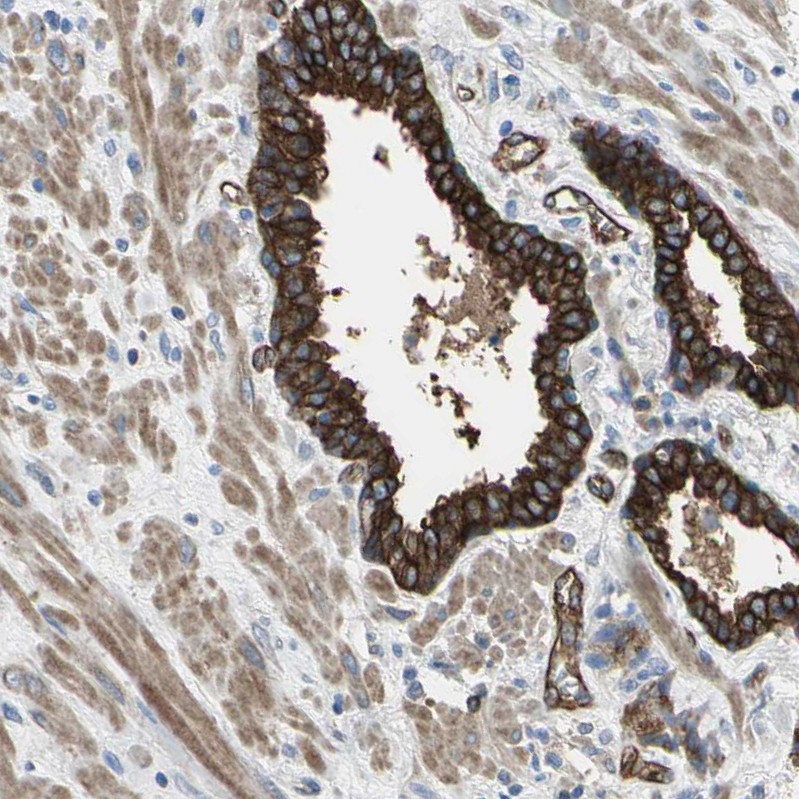

Immunohistochemistry analysis in human prostate and skeletal muscle tissues using HPA004747 antibody. Corresponding FLNB RNA-seq data are presented for the same tissues.